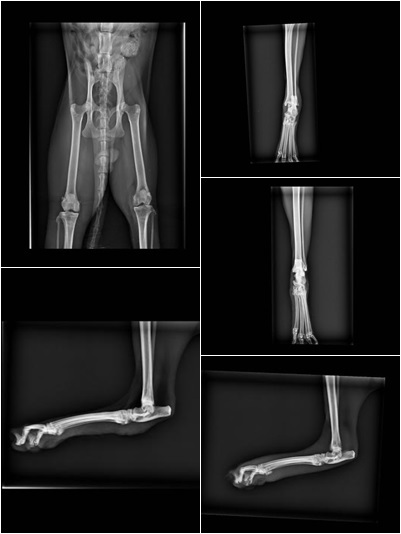

一開始小花進去時醫生說診斷他右後腳外傷 疑似被咬傷

精神狀況不好 有脫水的現象

左後肢頗行 可能是外側側韌帶斷裂

建議住院清創和抗生素治療

左腳復原的狀況很好

以後要野放回去也沒有問題

而右腳外傷就必須噴藥治療一段時間

一個月多後小花終於健康出院了^_^動物近況說明: 已原地置回原棲息社區,有外傷的腳已復原剩一點點痂皮,放回時行走正常,精神狀況良好,也有交代當地社區居民多觀察小花的狀況